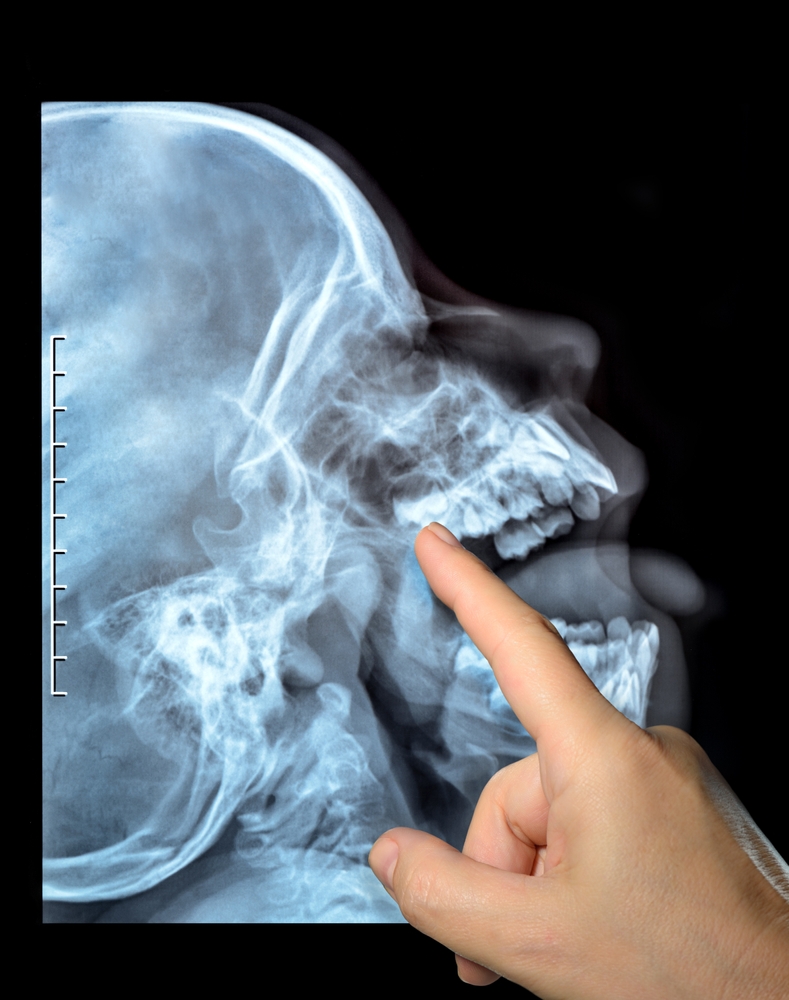

TMJ/TMD Temporomandibular Joint Disorder refers to a painful condition where the mastication muscles, the muscles that move the jaw, and the temporomandibular joints, the joints that connect the mandible to the skull, are not properly functioning.

Using TMJ advanced technologies and state-of-the-art equipment, our highly experienced TMJ expert at German Dental & Neuromuscular Clinic has helped many patients with TMJ misaligned problems, locking jaw, earaches, headaches, and many other symptoms resulting from TMJ Disorder. While TMJ Disorder is not life-threatening, it may lead to significant discomfort and tension if it goes untreated. Experiencing chronic pain may result in anxiety and depression.